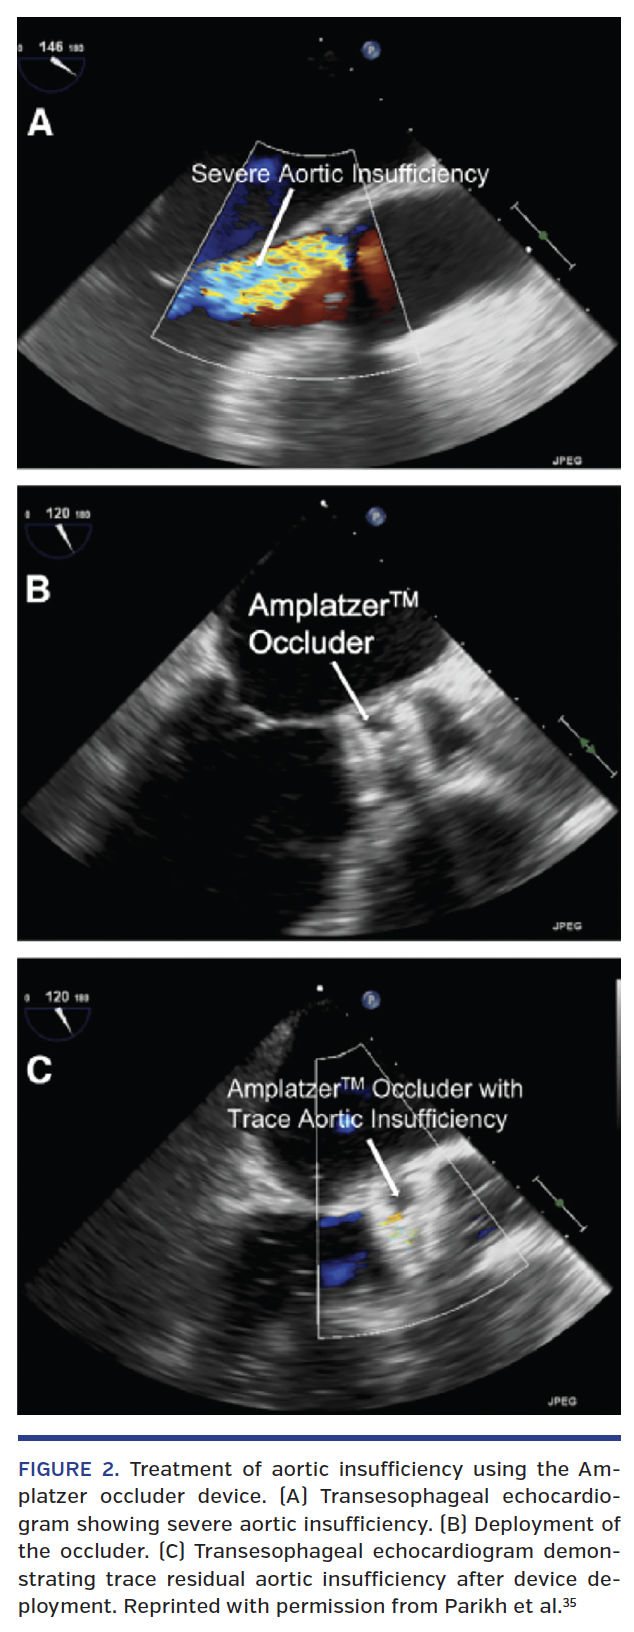

The International Heart and Lung Transplantation guidelines recommend surgical intervention with either aortic valve replacement or repair during LVAD implantation in patients who have greater than mild AI at baseline.28-30 In patients who develop AI after LVAD, so called de novo AI (Table 1), surgical treatment includes replacement with bioprosthetic valve31 (mechanical valves should be avoided due to high risk of thrombosis given low-flow state,24,32 valve repair using a coaptation stitch [“Park’s stitch”],33,34 or closure). While surgical management may be appropriate for many patients, re-do surgery is complex and high risk. Therefore, in select patients, less invasive, non-surgical transcatheter options must be explored. Transcatheter options for treatment of de novo AI include application of a septal occluder device to close the aortic valve or percutaneous transcatheter aortic valve replacement (TAVR).35-39 Grohmann et al first reported the use of an Amplatzer post-infarct muscular ventricular septal defect (VSD) occluder (St. Jude Medical) in a patient presenting with severe AI and symptoms consistent with congestive heart failure.35 The aortic valve was percutaneously closed via left subclavian approach under transesophageal echocardiographic (TEE) guidance using a 24 mm VSD occluder, sized using a preoperative computed tomography (CT) scan. While there was an improvement in the hemodynamics, the patient experienced significant transfusion-requiring hemolysis before ultimately being successfully discharged home.37 Since then, numerous studies have been published using the Amplatzer Cribriform device (St. Jude Medical). Russo et al described a patient who underwent surgical aortic valve repair 8 months post LVAD implantation and subsequently presented in cardiogenic shock 3 months later due to recurrent severe AI.36 Using transfemoral approach with a 7 Fr sheath, the left ventricular side of the Amplatzer occluder device was first exposed followed by the deployment of the aortic side under TEE guidance. The device was successfully deployed with no further AI and significant hemodynamic improvement. Subsequently, the group has published further results of their experience with the Cribriform device (Figure 2).35 In 5 patients with AI and excessively high surgical risk, percutaneous closure successfully improved AI (from severe to mild or absent; P=.04) with concurrent improvement in the hemodynamics. There were no changes in the LVAD parameters after the AV closure. In 1 of these patients, the device embolized to the aortic arch on day 4 and was successfully retrieved percutaneously. In this sick cohort, 2 patients were alive at 30 days with well-positioned devices and no residual AI. In a larger retrospective cohort of 10 LVAD patients with high surgical risk (STS mortality risk, 22%) and severe AI who underwent Cribriform septal occluder implantation, the 6-month survival was 30%.39 In this cohort, device-to-annulus ratio of less than 0.9 and lack of significant preoperative right heart dysfunction was associated with improved survival. Smaller devices may apply less pressure on the interventricular septum and hence may not affect the RV filling and outflow, leading to improved survival. It is important to note that with the Cribriform device deployed, the patient is fully reliant on the LVAD and a device malfunction can quickly become fatal.